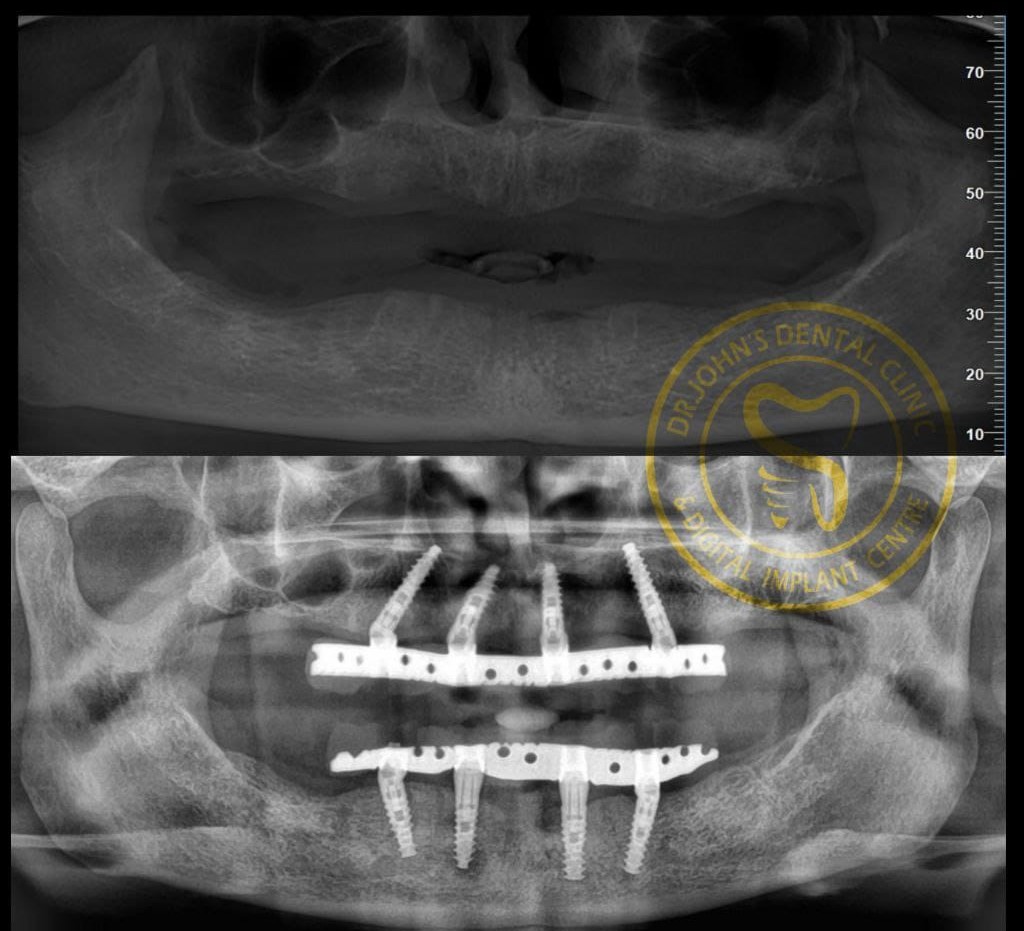

Expertise in Full Mouth Implants (All-on-4/6), Zygoma & Pterygoid implants, and Implant-supported prostheses.

Advanced implantology allows same-day teeth replacement or full-arch rehabilitation using the All-on-4 technique, providing quick and effective results.